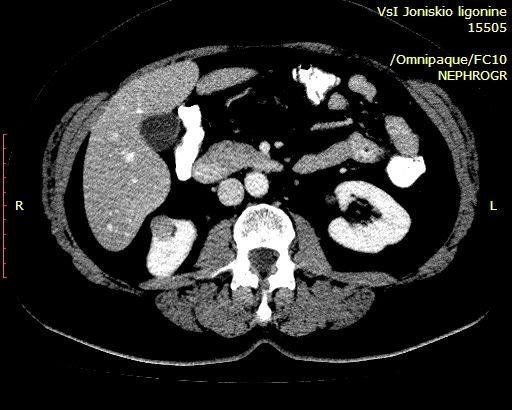

Женщина 55 лет, жалоб нет.

В нижнем полюсе правой почки обнаружено такое образование.

Немного похоже на AML, но неоднородное по структуре и с внутренним кровотоком, характеристики которого не в пользу RCC. Нет гипоэхогенного ободка, как при RCC.

Выполнена КТ с контрастированием.